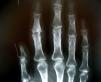

La media de seguimiento de los pacientes fue de 29 meses. Las indicaciones de cirugía incluyeron dolor con destrucción articular y disminución del balance articular. La edad media fue de 56 años. Del total de los pacientes 10 eran mujeres y 7 hombres. El diagnóstico preoperatorio fue de artrosis primaria (AP) en 8, artritis reumatoide (AR) en 4, artrosis postraumática (APT) en 3, y artritis psoriásica (AS) en 2. Los dedos intervenidos fueron el medio en 11 casos, el índice en 6 y el anular en 5. La patología estuvo distribuida por abordaje, patología y número de artroplastias de la siguiente manera: abordaje dorsal 7 AP, 3 AR, 2 APT, 2 AS; abordaje palmar 4 AP, 2 AR, una APT, una AS. El implante que se utilizó en todos los pacientes fue el modelo Avanta® (Avanta Orthopaedics, San Diego, California, EE. UU.). En una época previa, el abordaje dorsal suponía la técnica habitual en nuestra unidad para la realización de artroplastias de la AIP. Nos dimos cuenta del déficit de extensión que presentaban dichas artroplastias y decidimos entonces empezar a realizarlas por vía palmar. Actualmente todas las AIP realizadas en nuestra unidad se llevan a cabo por vía palmar. Decidimos valorar los resultados funcionales obtenidos con las últimas 8 artroplastias de AIP realizadas por vía palmar con un seguimiento mínimo representativo, y compararlas con aquellas con un seguimiento mínimo comparable realizadas en una época previa por vía dorsal. A pesar de que la selección de los pacientes fue consecutiva en el tiempo y que el grupo de la vía palmar fue el más recientemente intervenido, consideramos que la curva de aprendizaje que ha supuesto la ejecución de la vía palmar hace a este grupo comparable con el de la vía dorsal, que constituye pacientes intervenidos en años con un menor cúmulo de experiencia. La valoración clínica preoperatoria incluyó la magnitud del dolor y la amplitud de movimiento. La valoración del dolor se basó en la escala visual analógica (EVA), de 0 (ningún dolor) a 10 (dolor intenso). La media de las puntuaciones en la EVA preoperatoria fue de 6 (4-8). En la visita previa a la intervención se midió con goniómetro el arco de movimiento. Se calculó una media del arco de movimiento preoperatorio para los 22 dedos, cuyo valor fue de -15°/60°, siendo la extensión activa el primer valor, y la flexión activa el segundo valor. Utilizamos la media porque preoperatoriamente los 22 dedos tenían valores de recorrido articular sin dispersiones importantes, tratándose por ende de una muestra homogénea en ese sentido. En la última visita del seguimiento se valoró la satisfacción general de los pacientes de forma dicotómica como «satisfecho o no satisfecho». La EVA y el rango de movimiento se registraron y se compararon con los valores preoperatorios. La valoración radiológica consistió en proyecciones posteroanteriores (PA) (fig. 1), laterales y oblicuas de los dedos. Se valoraron la presencia o no de radiolucencias peri-implante, las osificaciones para-articulares, la rotura o no del implante y las desviaciones angulares.